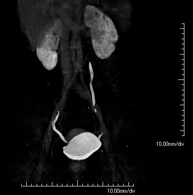

- Abdominal aorta CT angiography

A non-invasive diagnostic test that involves studying the abdominal aorta by obtaining high-definition anatomical images using CT (computed tomography) equipment and iodinated contrast. With the aid of workstations specialised for arterial studies, the image quality supports 2D and 3D reconstructions. It is indicated in patients with vascular disease (atherosclerosis), aortic aneurysms, abdominal pain of possible vascular origin, pre-surgical studies of lesions adjacent to the abdominal aorta as a vascular ‘map’, etc. Information obtained non-invasively is indispensable for patients requiring percutaneous or surgical processing. In patients who only require tracking of vascular lesions, this technique is the non-invasive technique of choice, together with MRI angiography.